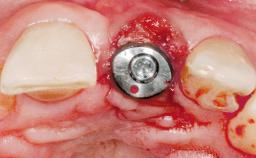

Late Placement of an Implant in a Maxillary Left Central Incisor Site

# of Implants 1

Type of Implants Two-Piece

Attachment Two-Piece

Placement Protocol Early or late implant placement